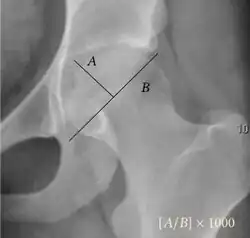

| Measurement | Image | Target | Normal value |

| Acetabular depth ratio |

|

Deepness of acetabulum. | >250

|